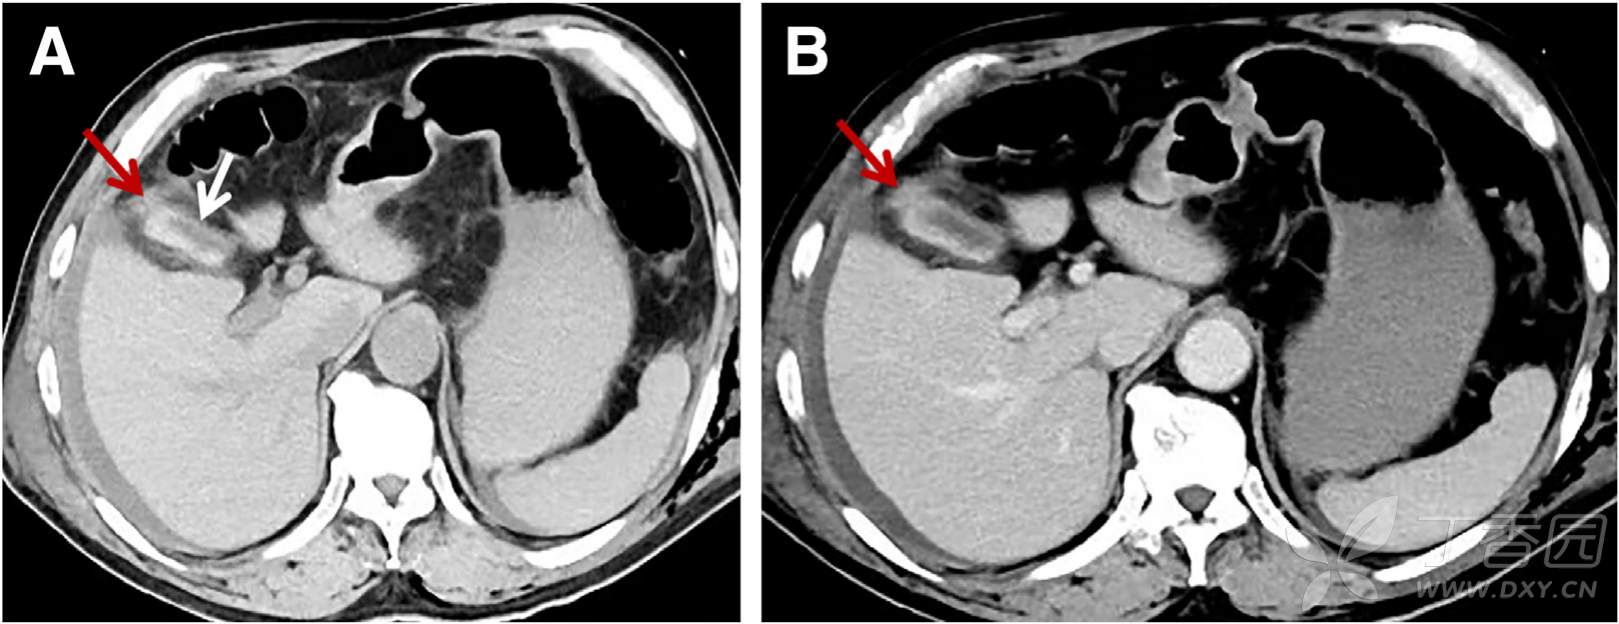

辅助检查:贫血(Hb 91g/L),肝功能异常(AST 254 U/L,ALT138 IU/L)。诊断性腹穿抽出血性及胆汁性腹水。腹部CT如下图:

请问:诊断是什么?

A 肝破裂 B 胆囊破裂 C 十二指肠破裂 D 腹腔内金属异物刺入